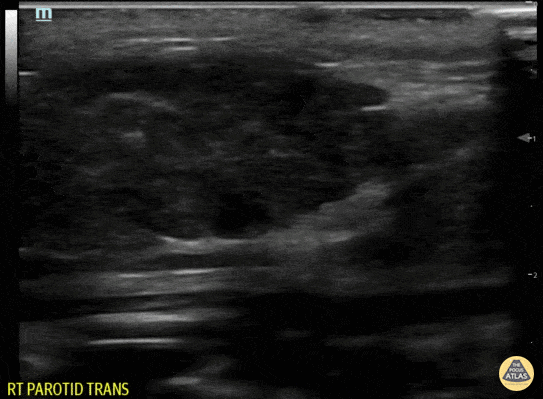

Right parotitis in a pediatric patient who presented with "jaw swelling". Contributor: Jaron Smith, MD, Phoenix Children's Hospital